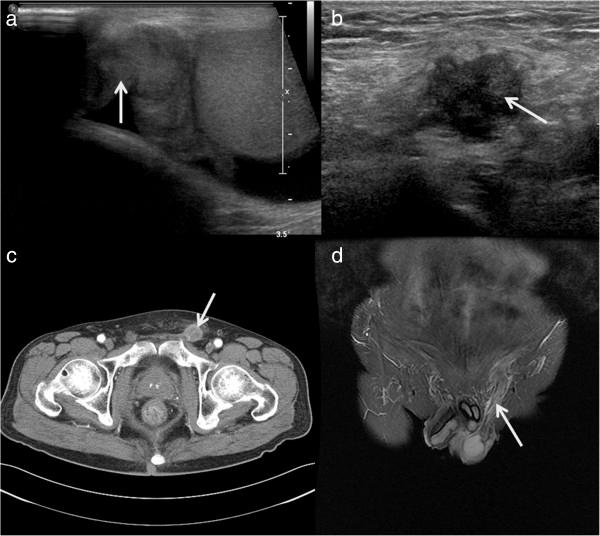

We recently observed two cases of late-onset metastatic adenocarcinoma of the spermatic cord. Both patients complained of groin discomfort with a palpable mass in the scrotum and inguinal area. Radical orchiectomy and adjuvant chemotherapy were performed in both patients. Although the prognosis of patients with metastatic adenocarcinoma of the spermatic cord is typically poor, the prognosis of our patients was favorable after follow-up for 14 to 18 months.

In patients with groin discomfort or swelling and a history of gastric cancer, metastatic adenocarcinoma should be included in the differential diagnosis for early detection of tumors.